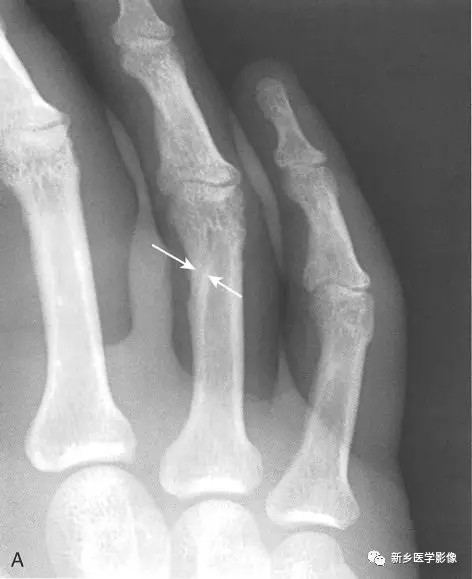

骨折线,从恰当的角度观察时,通常比骨骼中的正常线状影如滋养血管沟影

骨干的滋养血管沟,在骨干部分见低密度条 形透光区

第五掌骨基底骨皮质不连续,这个似乎比较可靠.骨内需注意血管沟.